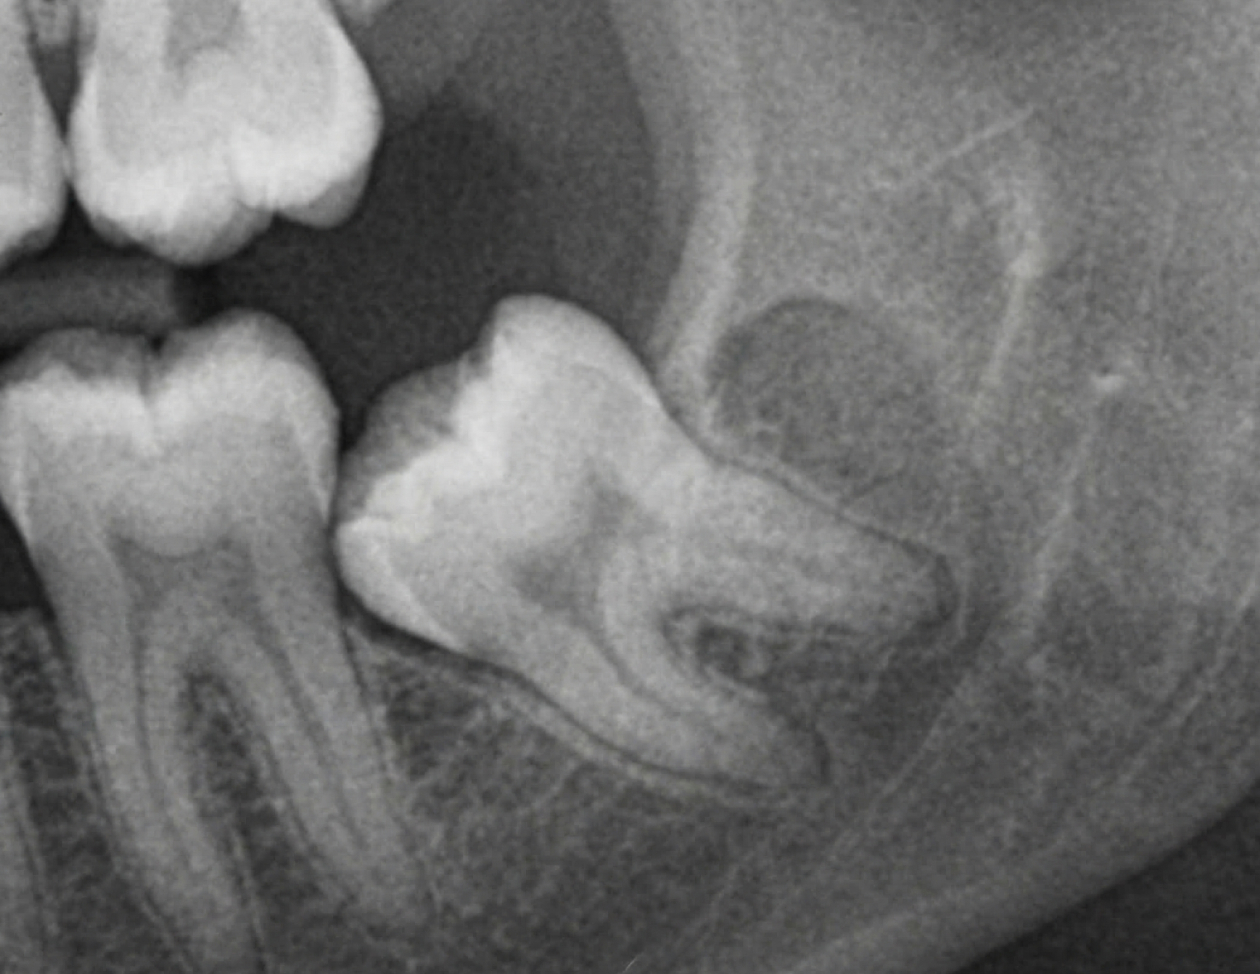

정확한 판단에서 시작하는사랑니 발치정확한 판단에서시작하는 사랑니 발치

TU치과는 사랑니를 ‘있으면 안되는 치아’로 보지 않습니다. 사랑니는 모든 경우에 반드시 발치해야 하는 치아는 아닙니다.

하지만 위치와 방향, 주변 치아와의 관계에 따라 반복적인 염증이나 장기적인 위험 요소가 될 수 있습니다. TU치과는 사랑니 발치 여부를 결정하는 정확한 판단에서 시작합니다.하지만 위치와 방향, 주변 치아와의 관계에 따라 반복적인 염증이나 장기적인 위험 요소가 될 수 있습니다. TU치과는 사랑니 발치 여부를 결정하는 정확한 판단에서 시작합니다.

정밀 진단 기반 접근

X-ray 및 CT 촬영 사랑니와 신경관의 거리 분석 뿌리 형태 및 난이도 평가 발치 난이도에 따른 계획 수립

사랑니 발치가 필요한 경우

아래 경우라면 사랑니 발치를 고려할 수 있습니다. 반복되는 통증·염증, 인접 치아 손상, 향후 치료(교정·보철·임플란트) 영향, 장기 관리의 어려움이 기준이 됩니다.